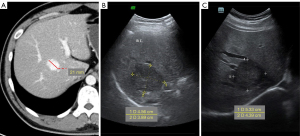

A hepatic nodule was incidentally detected in a 29-year-old man during an ultrasound examination while checking the condition of a hypoechoic lesion 3 years ago. The instant CT examination revealed a low-density nodule with a length of about 21 mm (Figure 1A). After 29 months of ultrasound follow-up, the length of the lesion increased to 46 mm (Figure 1B). The ultrasound and MRI with the contrast agent of gadobenate dimeglumine after 36 months showed a mass about 53 mm in length (Figure 1C). The patient had no medical history of chronic liver disease or cancer. The patient’s laboratory test results, including routine blood tests, blood biochemical examinations, and liver function tests, were normal.